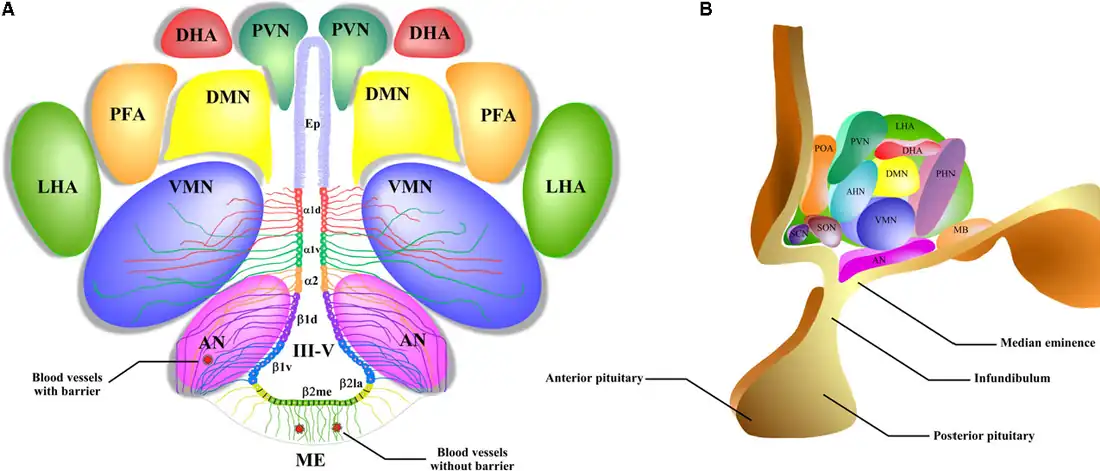

Núcleos neuronales

Los cuerpos de las neuronas hipotalámicas están agrupados en núcleos, los cuales disponen de proyecciones axonales con las que alcanzan otras regiones del encéfalo y otros núcleos hipotalámicos. Tal disposición permite la continua comunicación entre las neuronas del hipotálamo y otras áreas del cerebro.[36]

Desde el punto de vista anatómico el hipotálamo se divide en tres zonas principales: medial, lateral y periventricular. Los núcleos se concentran en las zonas medial y periventricular, las más relacionadas con la regulación central endocrina. A la zona lateral se le considera un «relevo» donde están establecidas conexiones del hipotálamo con los elementos encefálicos más rostrales.[37]

Son once los núcleos principales del hipotálamo y sus funciones permiten la «integración de las funciones del cuerpo para el mantenimiento de la homeostasis».[38]

| Zona[38] | Nombre[8][39] | Localización[39] | Función |

|---|---|---|---|

| Lateral | Núcleo hipotalámico lateral | Hipotálamo lateral | Actúa como el centro desde donde se regula la ingesta de agua y el apetito.[40][41] |

| Lateral Medial |

Núcleo preóptico | Área preóptica | Produce hormona liberadora de gonadotropinas (GnRH).[42] |

| Núcleo supraóptico | Anterolateral, arriba del tracto óptico | Produce hormona antidiurética o vasopresina.[6] | |

| Periventricular Medial |

Núcleo paraventricular | Periventricular anterior dorsal | Produce oxitocina, hormona antidiurética, Hormona liberadora de tirotropina(TRH), Hormona liberadora de corticotropina(CRH) |

| Núcleo arcuato | Hipotálamo basal medial cercano al tercer ventrículo | Interviene en la conducta emocional, libera GnRH. | |

| Medial | Núcleo supraquiasmático | Encima del quiasma óptico. | Regulación del ciclo circadiano. |

| Núcleo ventromedial/ventrodorsal | Ventromedial | Implicado en conductas defensivas y agresivas. Centro de la saciedad. | |

| Cuerpos mamilares | Porción más caudal del hipotálamo[43] | Participa en la memoria. | |

| Núcleo hipotalámico posterior | Hipotálamo posterior | Termorregulación. | |

| Núcleo hipotalámico anterior | Hipotálamo anterior | Termorregulación. | |

| Núcleo dorsomedial | Dorsomedial | Termorregulación. |